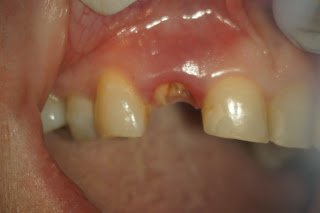

The endodontists at Superstition Springs Endodontics are skilled in restorative procedures closely associated with endodontic treatment. At your request, esthetic post and core buildups can be immediately placed following endodontic treatment.